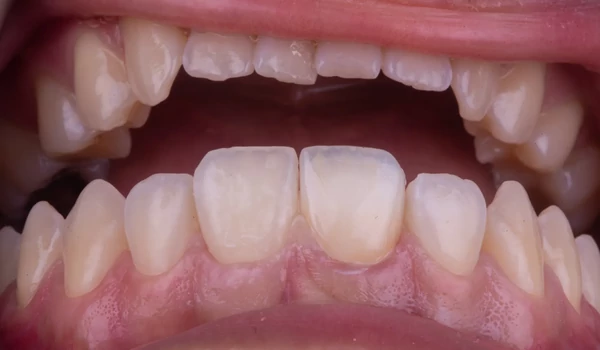

| A ragasztás maga a háromkomponensű PANAVIA™ V5 cementtel történt (23–28. ábra): Az előkészített fogstruktúrát és a felépítményt a PANAVIA™ V5 Tooth Primer-rel kezelték, a korona belső felszínét pedig a CLEARFIL™ CERAMIC PRIMER PLUS-szal. Végül a PANAVIA™ V5 Universal (fehér) cementet kinyomták a koronába, majd a koronát a helyére illesztették. A felesleges cementet a legjobb a gél fázisban eltávolítani – azaz a végső fényre keményítés előtt, 3-5 másodperces rövid polimerizáció után. Alternatív megoldásként közvetlenül a restauráció behelyezése után is eltávolítható ecsettel vagy hasonló eszközzel. Ebben az esetben az első lehetőséget választották. A kezelés eredményét a kofferdám eltávolítása, valamint a végső klinikai és esztétikai értékelés után a 29. ábra mutatja. |

29. ábra. A kezelés eredménye közvetlenül a kofferdám eltávolítása után. |

KonklúzióA beavatkozás célja egy traumásan sérült fog megőrzése volt – mind funkcióban, mind esztétikában. A sikerhez kulcsot jelentett a CLEARFIL MAJESTY™ ES-2 Premium erős, stabil alapja és a PANAVIA™ V5 egyik legmegbízhatóbb ragasztórendszere kuraraynoritake.eu. |